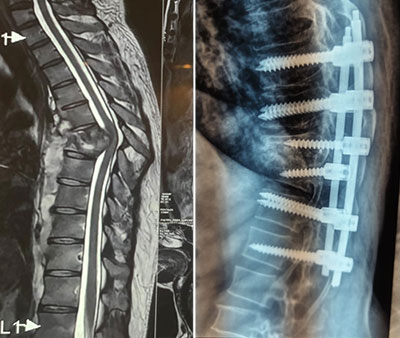

Spinal Tuberculosis

Spinal Tuberculosis, or Pott’s Disease, is a severe form of tuberculosis that affects the spine, leading to vertebral destruction, spinal deformity, and neurological deficits. Dr. Naik is skilled in diagnosing and treating this rare yet debilitating condition. Treatment typically involves a combination of anti-tubercular medication and, in more advanced cases, surgical intervention to stabilize the spine and prevent further damage. Surgery may include decompression of the spinal cord, abscess drainage, and spinal reconstruction to prevent or correct deformities such as kyphosis.